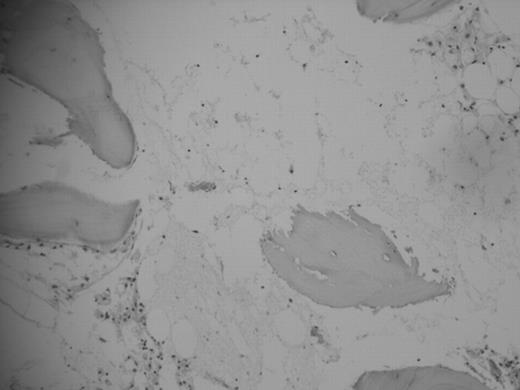

The exact incidence is unknown, but more than 200 cases have been reported in the world literature and the molecular test for diagnostic where performed only in a very few of them. Thirty-five years old woman with multiple fractures in right leg from a car accident was treated in her rural town, she received a fresh whole blood transfusion from her sister and then went for surgery, antibiotics and analgesia where given; six days after she developed erytroderma in the upper chest, two days later generalized bone pain and weakness were aggregated, the next day erithroderma generalize and started with diarrhea and jaundice; her evolution was torpid with fever, more weakness and jaundice, pallor, purpura and oropharyngeal pain. She was sent for hematological evaluation to our tertiary care institution, and a TA-GVHD was considerate; a work up on that was performed and the CBC showed pancytopenia, LFT with elevation of bilirubins, transaminases and alkaline phosphatase; the bone marrow aspiration and biopsy with aplasia, the skin biopsy with lymphoid infiltration, junction of epidermis with dermis was intact and no leukocytoclastic vasculitis. She received methylprednisolone, cyclosporine, filgrastim, wide range antibiotics and amphotericin B, leukoreduced and irradiated blood products. Her evolution was torpid with deterioration of her conditions and 48 hour later she died of septic shock. There is no effective treatment for TA-GVHD and no difference between early o delayed diagnostic, the evolution is almost always fatal, that is why the prevention is needed with the leukoreduction and irradiation of blood products, specially in recipients with clear risk for development of TA-GVHD: congenital immunodeficiencies, fetuses y newborns, hematological cancers, solid tumors in chemotherapy, hemopoiectic and solid organ transplanted, and first and second degree relatives. Better policies, technology, education for the primary care physician and access to blood products with high quality is needed to prevent this type of complications, specially in rural areas where transfusions with whole fresh blood from relatives are performed commonly.